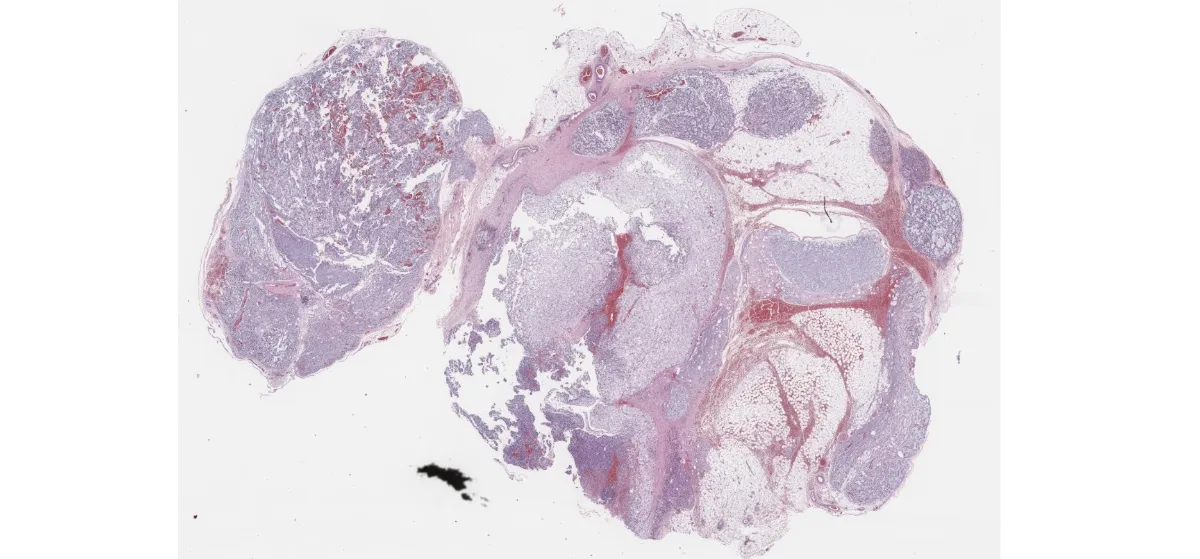

En la biopsia se observa una lesión multinodular, no encapsulada, con estroma mixoide y vasos en patrón plexiforme. Se identifican células pleomórficas, algunas multinucleadas, con citoplasma microvacuolado, dispuestas en patrón laxo. La inmunohistoquímica muestra positividad para S-100 (heterogénea), p16 (intensa), SOX9, andrógenos y SF-1, con un Ki67 del 25%. Mitosis ocasionalmente atípicas. Negatividad para múltiples marcadores epiteliales, musculares y neuroendocrinos.

HE – biopsia (1)

HE – biopsia (2)